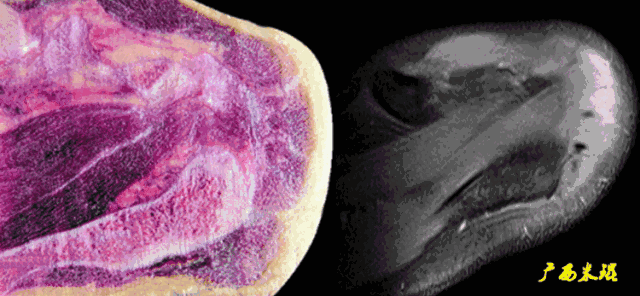

2、斜矢状位:垂直于冈上肌长轴,观察肩峰形态及喙肩弓,观察肩袖4个组分的短轴断面。

各个序列肩袖均表现为均匀的低信号,是肌腱的延续。